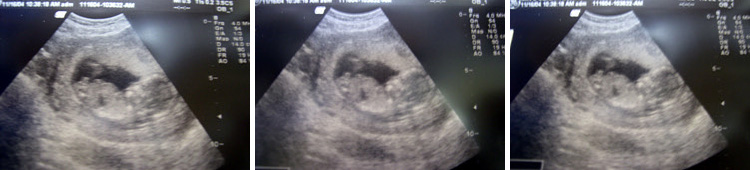

임신 14주 (2004년 11월 16일 화요일 병원을 다녀와서..)

<center><b> CRL = 7.5cm </b></center>

척주뼈도 선명하게 보이고 심장박동소리도 씩씩하고..옆얼굴선도 뚜렷해지고...

이젠 엄마배로 널 볼수있게 되었단다.